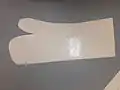

Orthotic Template

Orthotic Template LTT Template

LTT Template LTT cooling after moulding